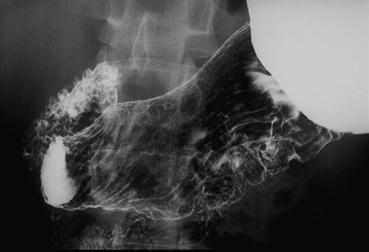

Criteria of Hist.ClassificationMalignant epithelial tumor/Signet-ring cellcarcinoma

LocationStomach/Angle

Technique, MethodX-ray

Macroscopic TypesType 0/IIc (IIc) Superficial depressed type

Size30 - 34

Depth of Tumor Invasionmucosa